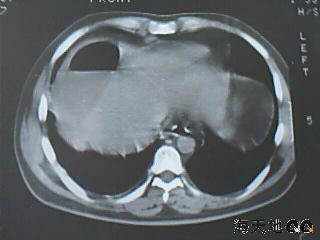

右肝膈顶区液气平面.右膈肌增厚改变,病灶下部层面呈半月形延伸于肝表面.且于横结肠无明确密度切关系.

右隔肌与肝顶之间隙有长气液平,其下散在点状气体影,右侧腹膜局限增厚。考虑右膈下脓肿。

右膈肌增厚,肝膈间见条状低密度影内可见积气影及宽大液平面,并未见与结肠相连。因此考虑膈下脓肿。